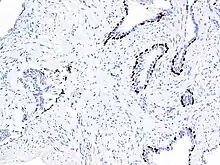

p63 immunostaining has utility for head and neck squamous cell carcinomas, differentiating prostatic adenocarcinoma (the most common type of prostate cancer) and benign prostatic tissue;[23] the nuclei of the basal cells of normal prostatic glands stain with p63, while the malignant glands in prostatic adenocarcinoma (which lacks these cells) do not.[24] P63 is also helpful in distinguishing poorly differentiated squamous cell carcinoma from small cell carcinoma or adenocarcinoma. P63 should be strongly stained in poorly differentiated squamous cell, but negative in small cell or adenocarcinoma.[25]

Cytoplasmic staining on immunohistochemistry is seen in cells with muscle differentiation.[26]